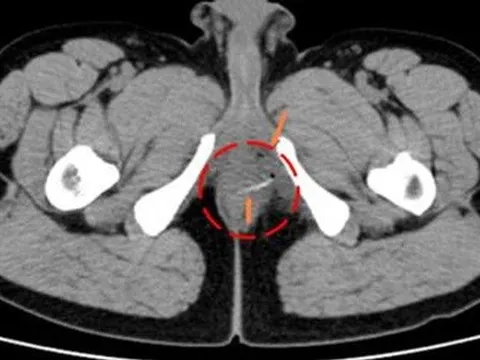

Ớn hình ảnh xương cá chắn ngang hậu môn

Một người đàn ông đi khám sức khỏe định kỳ được bác sĩ phát hiện xương cá đâm ngang trực tràng hậu môn sau khi chụp CT toàn thân.